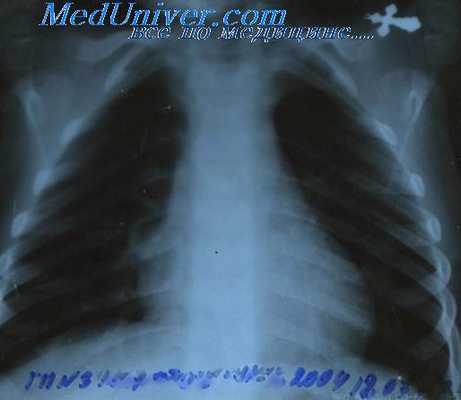

Рентгенография органов грудной клетки при лимфогранулематозе в двух проекциях проводится для выявления поражения медиастинальных лимфатических узлов, легких и плевры.

- Инструментальные исследования. При туберкулезе на рентгенограмме легких отмечается увеличение прикорневых, медиастинальных лимфатических узлов, инфильтрация верхних долей легких, иногда выпот в плевральную полость. При мононуклеозе и гемобластозах на УЗИ брюшной полости обнаруживается выраженная спленомегалия, реже гепатомегалия.

Рентгенологические исследования дают ценные указания для стадиализации болезни. Рентгенографии легких показывают медиастинальные или паренхиматозные локализации. Костные рентгенографии и бариевое исследование гастроинтестинального тракта выявляют детерминации на этих уровнях. Для общего контроля больного, производятся также уро-графии и кавографии, которые, вместе с лимфографией дают наиболее полную картину ганглиозных субдиафрагмальных детерминаций.